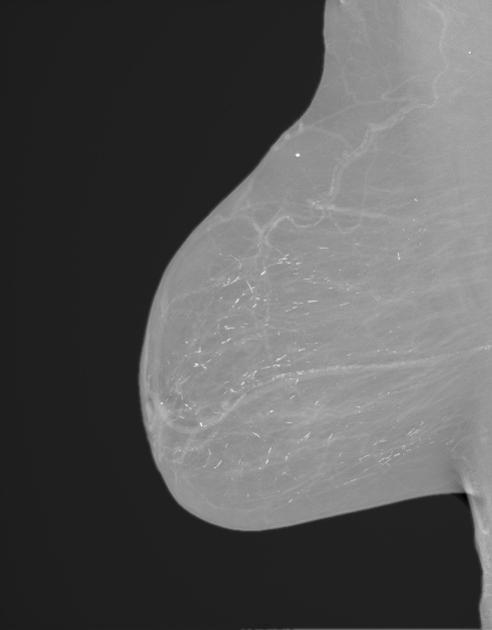

Diagnosis?

Hamartoma (fibroadenolipoma).

Glandular and fatty tissue.

No.